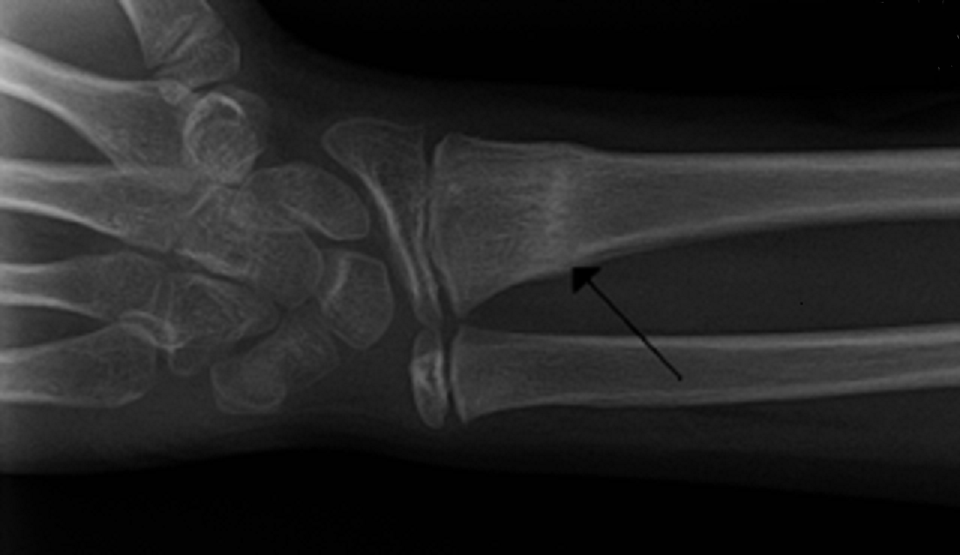

A common childhood injury after a fall is a radial fracture. Also known as a torus, greenstick, or buckle fracture, this break occurs when a child reaches out with his hand to cushion a fall. Since a child’s bones are still relatively soft when compared to an adult, the bone compresses, causing a flattening appearance on xray (see above picture). The child oftentimes will continue to use the arm, although he or she may favor it somewhat. Pushing directly over the fracture site in the forearm will elicit pain. Treatment is usually 3 to 4 weeks in a short arm cast or rigid splint, and these fractures usually heal very quickly without any permanent deformity. Family practice physicians trained in non-surgical orthopedics can adequately manage these simple fractures for a fraction of the cost when compared to an emergency room (see a previous article, The Case for Limited Emergency Room Use) or orthopedic specialist.